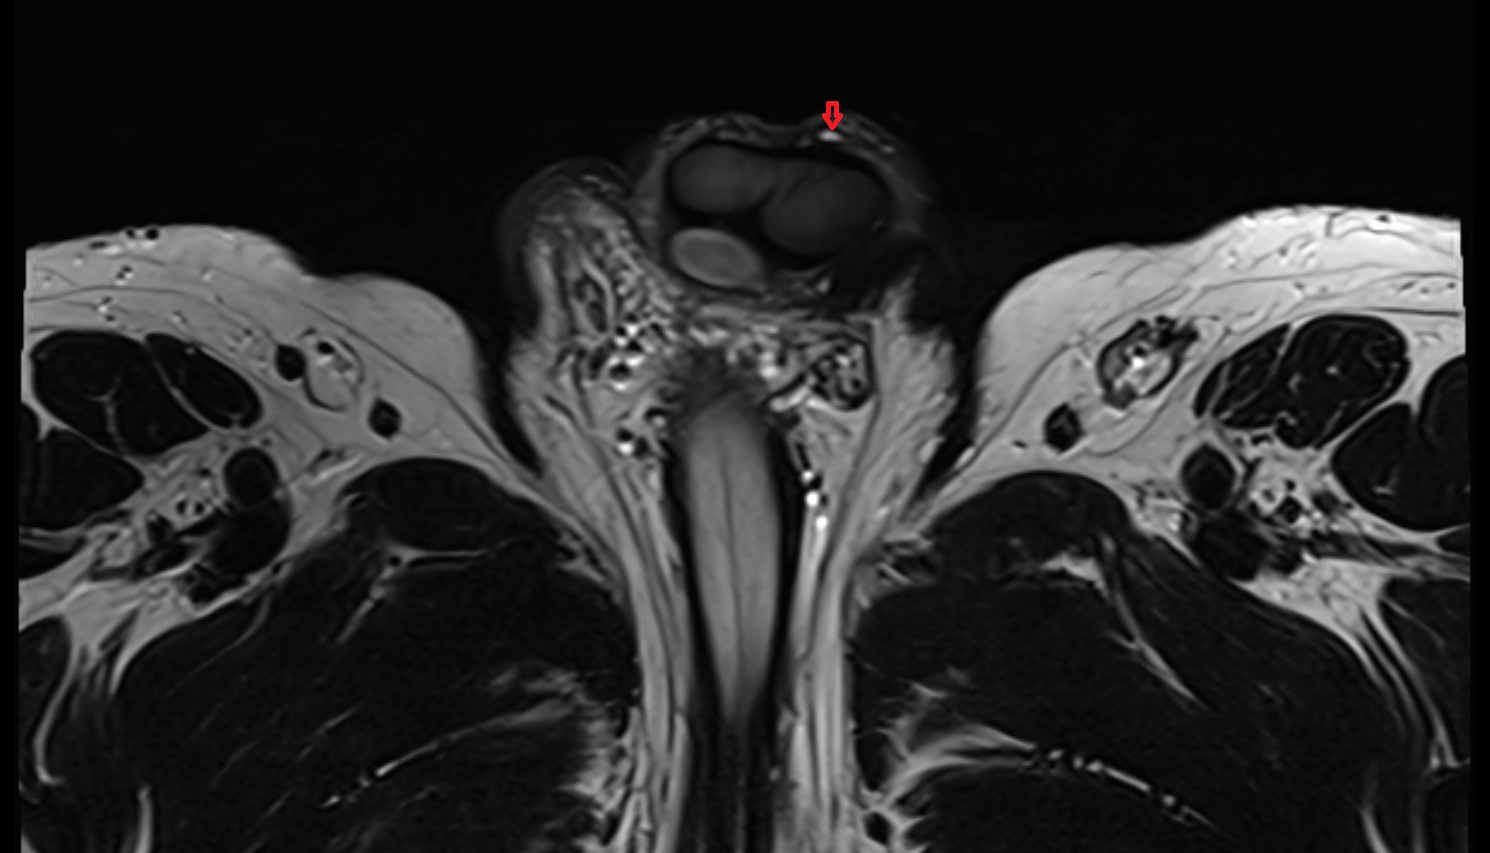

- Peripheral zone of prostate

- Anterior Fibromuscular Stroma of prostate

- Central zone of prostate

- Transitional zone of prostate